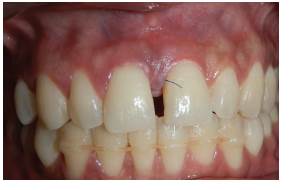

Se hace valoración clínica completa, se procede a realizar asepsia de la zona, aplicación de lidocaína al 2 % 1:80.000, mediante técnica anestésica infiltrativa se realiza incisión con hoja de bisturí número 15. Se levanta colgajo de espesor total para exponer la lesión; posteriormente aflora tejido nodular único, de consistencia firme y depresible, sangrante, doloroso a la palpación, de color rosa, de 4 mm de ancho por 9 mm de largo, de superficie lisa, base sésil. Se hace la extirpación completa de la lesión (figura 2A). Se realiza raspado y alisado radicular ultrasónico y manual. Se efectuó detoxificación de la raíz con fórmula magistral de ácido cítrico gel al 3 0% y hemostasia por dos minutos (figura 2B). Se sutura con Nylon 6-0 con puntos en ocho (figura 3A). Se realizó cita de control 8 días después de la cirugía para retirar suturas (figura 3B). Se cita nuevamente a los 15 días para realizar seguimiento. Se evidenció cicatrización de los tejidos blandos, y dos meses después se encontró un proceso de cicatrización dentro de lo esperado, sin complicación alguna.